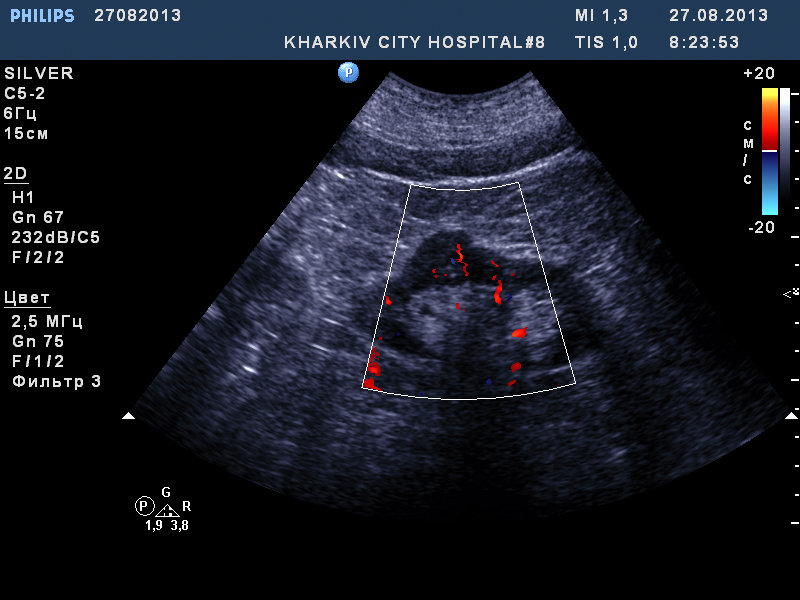

собственно такая картина.

если мой прицел не сбился, вероятно ПКР.

Рекомендовал КТ.

Сосудистый рисунок сохранен на сонограммах 1 и 2.